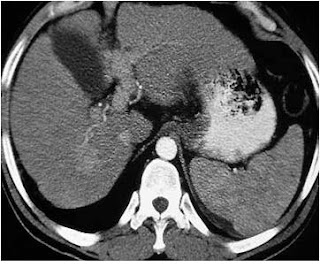

ÒLa TC muestra una masa con menor valor de atenuacion que el parenquima circundante.

ÒA veces el tumor se presenta con una densidad similar al higado normal, en estos casos su detección depende de los cambios en el contorno hepático y de otros signos secundarios.

ÒLa lesion tiene con frecuencia areas centrales con menor valor de atenuación.

ÒUna de las características de los hepatocarcinomas es en general el tener una vascularización arterial exclusiva (tumor hipervascular). Luego de la inyección con el medio de contraste, durante la fase arterial pura, los tumores hipervasculares se resaltan más que el hígado normal, que está vascularizado principalmente por vía portal.

ÒLos tumores hipervasculares aparecen hiperdensos en esta fase ar

terial.